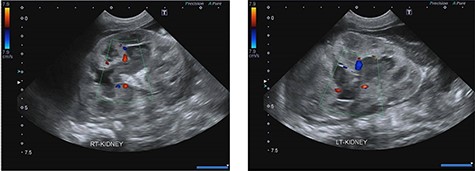

A 34-week preterm male infant was delivered by cesarean section due to fetal distress. He was admitted to the neonatal intensive care unit (NICU) due to neonatal sepsis and mild acute respiratory distress syndrome. He received gentamicin and amikacin for a week despite his hemoculture, sputum culture and urine culture revealing no growth. His clinical condition improved following treatment. Twenty-one days later he developed feeding intolerance, oliguria, a history of non-foul-smelling diarrhea, fever and alteration of consciousness. A physical examination found a body temperature 39.3°C, tachycardia and tachypnea. Laboratory examinations showed hyponatremia (Na 119 mEq/L), hyperkalemia (K 10.5 mEq/L), metabolic acidosis (HCO3 11 mEq/L) and azotemia (BUN 31.6 mg/dL) with acute kidney injury (Cr 5.1 mg/dL). The urinalysis revealed pyuria and yeast cells. Urine and hemoculture demonstrated C. albicans. The patient was transferred to the Pediatric Intensive Care Unit, where ultrasonography demonstrated a dilated renal pelvis and calyx in both kidneys and bilateral echoic lesions with central hyperechoicity, suggestive of fungal bezoars (Fig. 1) and a large amount of ascites. He was given intravenous fluconazole, normal saline boluses, potassium correction, sodium bicarbonate boluses and ultrasound-guided ascites aspiration was performed. After resuscitation and initial treatment, his serum creatinine decreased to 1.22 mg/dL and his blood culture was negative, however, urine culture continued to show the presence of C. albicans. Re-imaging showed bilateral complicated perinephric fluid collections and a large number of intra-abdominal fluid collections. The patient underwent a bilateral percutaneous nephrostomy. An antegrade pyelography found a filling defect in the bilateral pelvocalyceal system with contrast extravasation at the upper and lower poles of the left kidney (Figs 2 and 3), following which his creatine improved to 0.37 g/dL. After that, the patient underwent a left pyelotomy (flank incision) with bezoar removal and PCN replacement with a left double J stent. Two weeks later, we performed an open right pyelotomy and double J stent insertion via a flank incision. After the operation, his symptoms improved and his creatinine decreased to 0.27 mg/dL. Tissue pathology from the renal pelvis revealed fungal balls consisting of Candida spp. (Fig. 4). After 167 days of admission, he was discharged from the hospital with serum creatinine of 0.30 mg/dL.

Ultrasonography shows echogenic lesions in dilated renal pelvis and calyces, bilaterally.